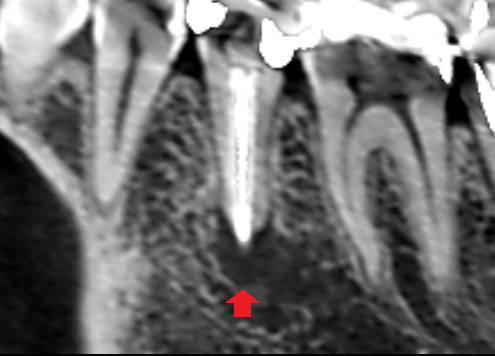

下顎第二小臼歯の初診時の矢状断のCT画像です。

赤い矢印の先に膿の影がみられます。